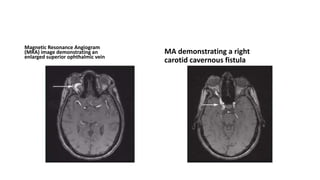

Magnetic Resonance Angiogram

(MRA) image demonstrating an

enlarged superior ophthalmic vein

MA demonstrating a right

carotid cavernous fistula

Magnetic Resonance Angiogram (MRA)image demonstrating an enlarged superior ophthalmic vein MA demonstrating a right carotid cavernous fistula